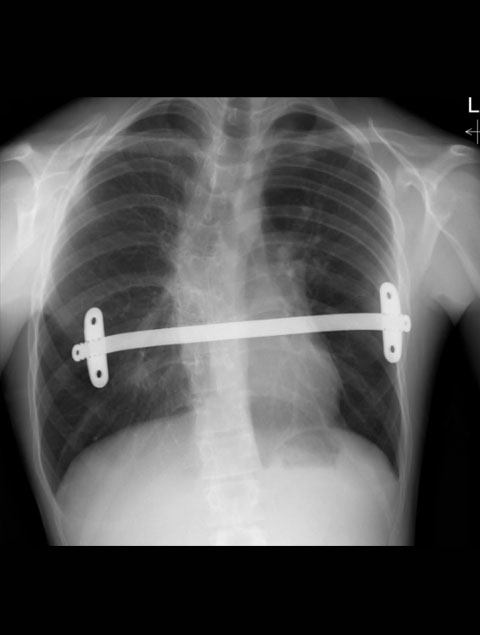

A Nuss Procedure [pectus Excavatum] with associated scoliosis

Joao, 19 years old with an asymmetric pectus excavatum and associated quite severe spinal scoliosis

Chest CT sagittal view showing extent of scoliosis